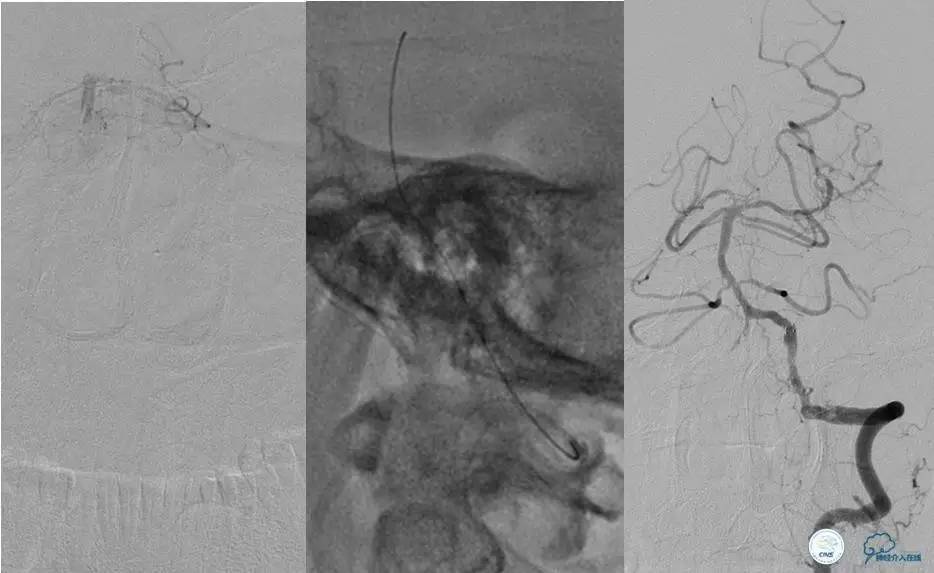

造影评价血管、判断闭塞段,微导丝小心穿过闭塞段,微导管造影,交换技术,球囊扩张,Enterprise支架。在后扩张时导丝刺破M3段血管,蛛网膜下腔出血(SAH)。

微导管进入破裂血管,栓塞弹簧圈1枚,出血停止,结束手术。继续双抗,术后2天肌力2级,神经功能恢复明显加快。

术后即刻和6天后CT,患者无明显临床症状。

半年后复查造影,无支架内再狭窄,可见弹簧圈,患者恢复至自己柱杖行走。

左侧颈内动脉末端闭塞,末端圆钝且有一定成角,开通难度较大,多次尝试导丝才成功穿过闭塞段。

开通效果很满意,术后症状明显恢复。

导丝很容易通过闭塞段。

顺利置入Wingspan支架,成功开通,手术顺利。